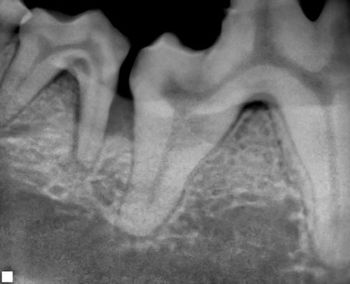

Visual examination, anesthetized probing and intraoral radiography can help veterinarians assess each patient's level of disease.

Visual examination, anesthetized probing and intraoral radiography can help you assess each patient’s level of disease.

The degree of severity of periodontal disease relates to a single tooth; a patient may have teeth that have different stages of periodontal disease. Here is an outline of the American Veterinary Dental College-approved periodontal disease classifications.